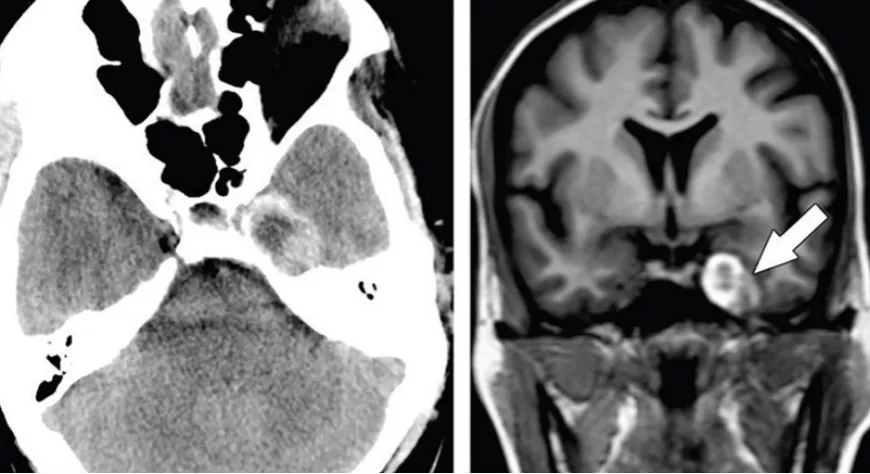

橙子大的腦膜瘤,如同一顆危險的果實,深深扎根于“手術(shù)禁區(qū)”——海綿竇深處,影像上看似乎占據(jù)了其顱內(nèi)的四分之一。在如此復雜位置生長出如此巨大的腫瘤,實在是難。

(術(shù)前MRI)

圖:海綿竇腦膜瘤合并左側(cè)頸內(nèi)動脈狹窄,手術(shù)難度大

圖1:病灶在t1加權(quán)像上呈低信號,周圍有高信號,在t2加權(quán)像上呈高信號且不均勻。增強檢查除了病灶邊邊緣輕微強化,未見增強。病變壓迫海綿竇內(nèi)頸動脈(ICA)。